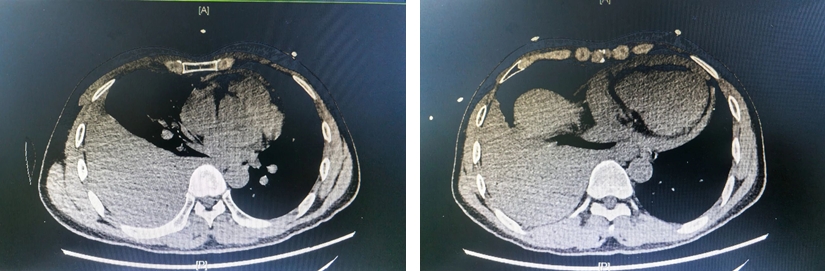

当日凌晨2时33分,急诊科戴何兴副主任医师接诊一名51岁右胸刀刺伤男性患者。患者入院后迅速出现休克体征,CT检查显示其右侧胸腔及心包腔大量积血。戴何兴立即启动创伤急救绿色通道,同步呼叫心胸外科紧急会诊。

手术探查证实,锐器贯穿患者右侧第四肋软骨直刺右心房,形成3厘米喷射状破口,瞬时失血量达2500毫升以上。麻醉科黎达锋主任团队采用自体血回输技术,在患者血液循环系统濒临崩溃时,及时维持并稳定了其生命体征。陈厚赏主任果断采取胸骨正中切口,精准找到出血点控制止血,修复右心房裂口。患者心率、血压逐渐稳定,手术后转至重症医学科监护治疗。1天后患者病情稳定,转回心胸外科普通病房康复治疗。

陈厚赏主任介绍,术中探查证实利器贯穿患者右侧第四肋软骨直抵右心房,造成长约3厘米的喷射状破口,这类手术的核心在于心胸外科团队对解剖结构的精确把控和决断力。此次手术,从开胸到完成心脏修补仅用时18分钟,体现了我院心胸外科团队对心脏外伤救治流程的标准化训练成果。麻醉科黎达锋主任团队采用自体血回输技术配合加压输血,实时调整输血策略,在患者术中出现循环衰竭的危急时刻,成功维持了其生命体征。